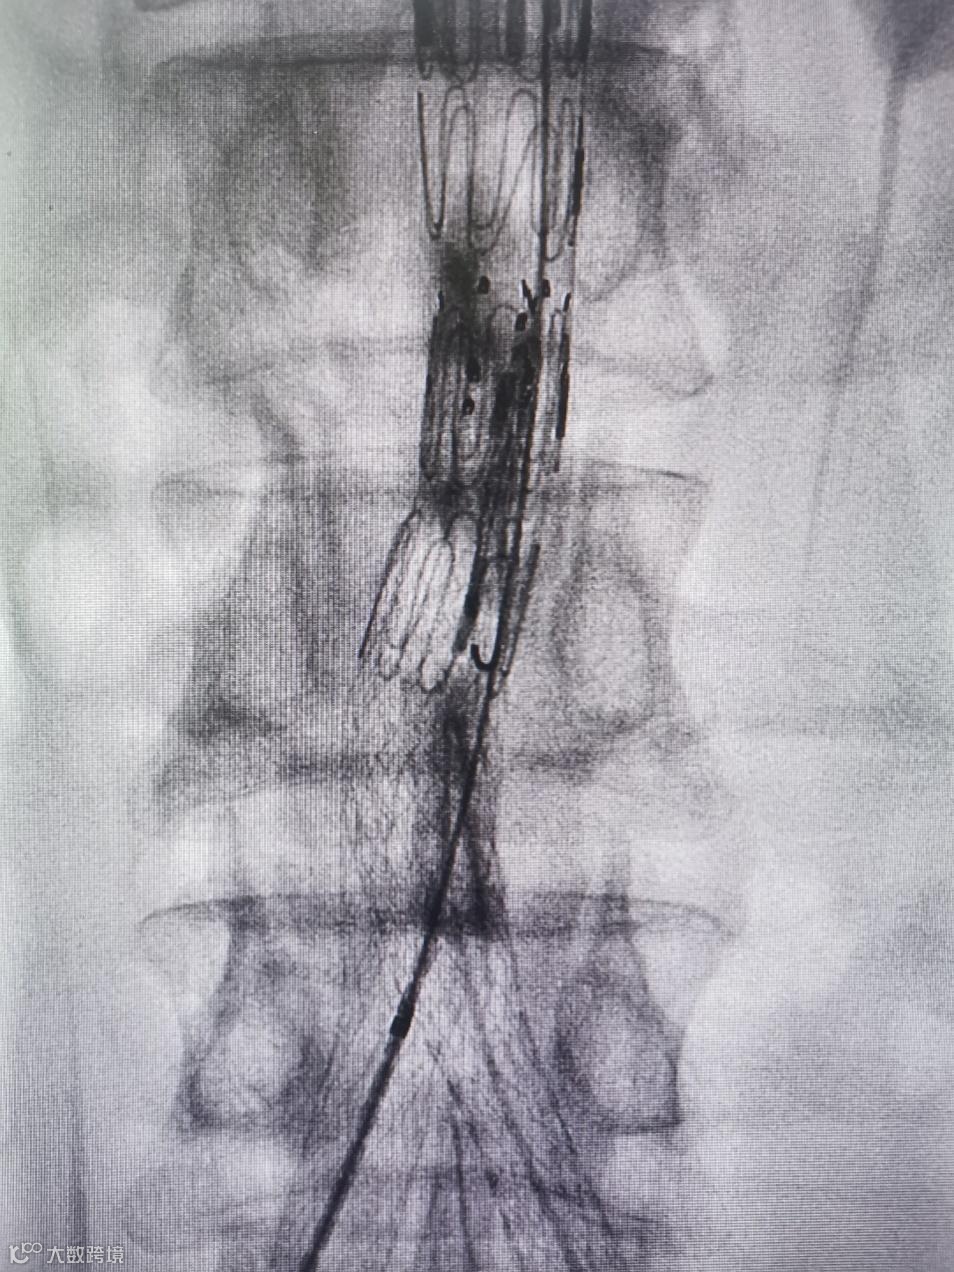

Separator With Aspiration catheter for Mechanical Thrombectomy(MT)【分离器辅助导管抽吸技术】:旨在提高整体系统的抽吸效率和治疗安全性,快速帮助血栓清除。

1)抽吸导管头端堵管,分离器可以快速疏通导管,降低撤管冲洗的频率。

2)针对大负荷血栓或亚急性血栓,分离器辅助下抽吸能提升整体系统抽吸效率,缩短手术时间。